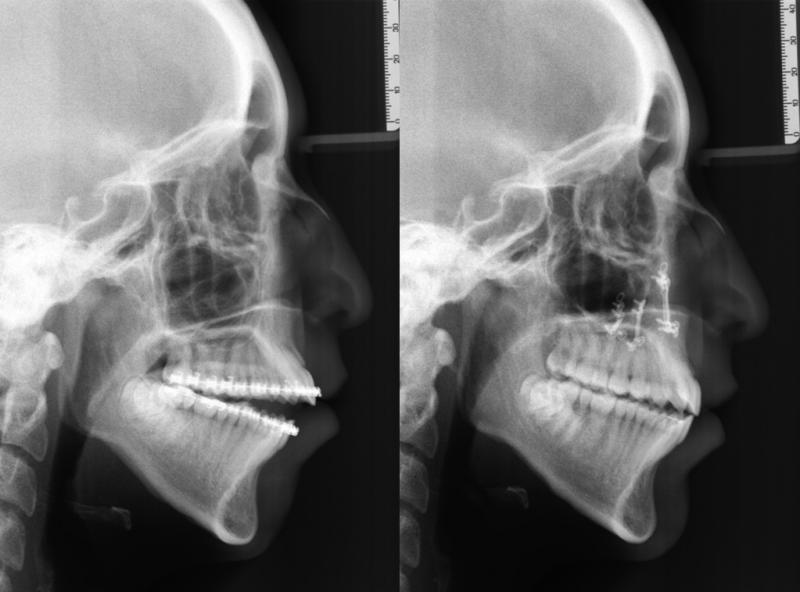

Diagnosis and treatment of dysgnathia, and orthognathic reconstructive surgery, genioplasty, maxillo-mandibular advancement/set-back, and surgical correction of facial asymmetry (See Images Below)

Orthognathic Surgery (Class II)

Orthognathic Surgery (Class III)

Orthognathic Surgery (Class II with 'Gummy Smile')